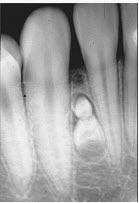

位于上颌侧切牙与尖牙之间的非牙源性囊肿(影像检查如图)是()。